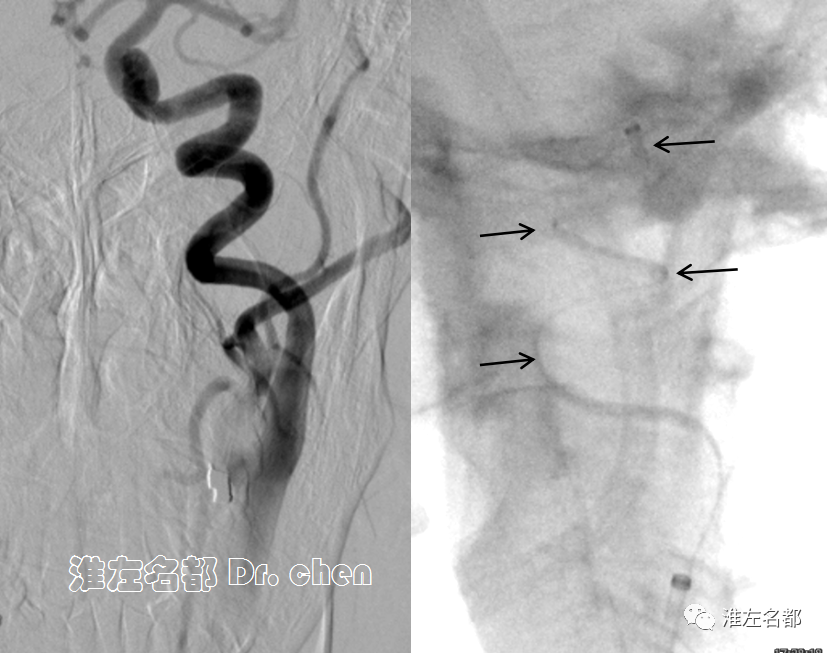

△采用同轴技术将6F长鞘(90cm,Cook)送至左侧颈总动脉,造影:左侧颈内动脉颅外段螺旋样延长迂曲,经.035”泥鳅导丝将中间导管(Navien 072, 105cm)头端送至岩骨段(黑箭)。

△经中间导管造影:左侧大脑前动脉A2段闭塞(橙箭)。

△经微导管释放取栓支架 S AB 4*20mm,造影:闭塞再通,局部管腔狭窄(橙箭)。

△30分钟后造影:左侧大脑前动脉前向血流良好,A3段局部中度狭窄(橙箭)

静推欣维宁15ml,7ml/h维持,30分钟后造影可见左侧大脑前动脉前向血流良好,A3段局部中度狭窄,解脱取栓支架。